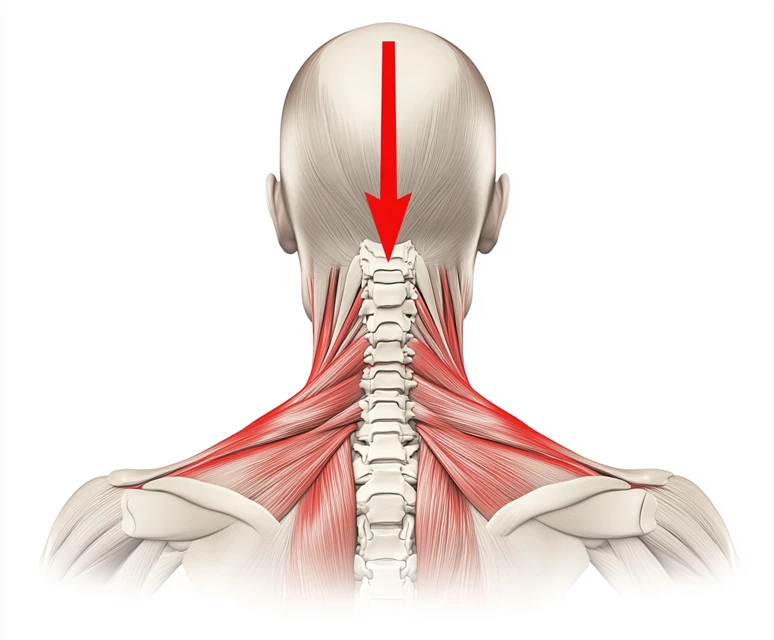

목디스크의 증상은 일반적으로 몇 가지 초기 신호로 나타납니다. 이를 조기에 인지하고 대처하는 것이 매우 중요합니다. 특히 다음과 같은 증상이 나타난다면, 즉시 전문가의 진료를 받는 것이 좋습니다. 목디스크는 주로 목의 디스크가 찢어지거나 탈출되면서 발생하는데, 이로 인해 주변 신경이나 척수에 압박이 가해지는 경우가 많습니다. 주요 초기 신호는 다음과 같습니다:

- 목의 통증: 목디스크의 가장 일반적인 초기 증상은 목의 통증입니다. 이 통증은 지속적일 수도 있고, 특정 자세를 취할 때 더욱 심해질 수 있습니다. 일반적인 근육통과는 다르게, 목의 통증은 종종 뻣뻣함과 함께 오는 경우가 많습니다.

- 어깨와 팔의 방사통: 목디스크로 인한 신경 압박으로 인해 어깨나 팔로 방사되는 통증을 느낄 수 있습니다. 이러한 방사통은 날카롭거나 찌릿한 느낌이 들며, 특히 팔을 움직일 때 그 강도가 증가할 수 있습니다.

- 머리의 통증: 목디스크의 통증은 두통으로도 이어질 수 있습니다. 특히 긴장성 두통과 비슷한 유형의 두통이 발생할 수 있으며, 이는 경추가 제대로 기능하지 못할 때 나타납니다.